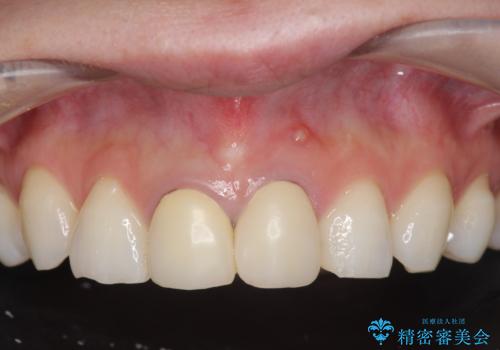

[ 前歯セラミック治療 ]白く不自然な前歯をきれいにしたい